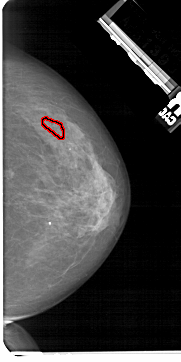

A_1465_1.LEFT_MLO

LEFT_MLO LINES 5491 PIXELS_PER_LINE 2911 BITS_PER_PIXEL 12 RESOLUTION 43.5 NON_OVERLAY

FILE: A_1465_1.RIGHT_MLO.OVERLAY

TOTAL_ABNORMALITIES 1

ABNORMALITY 1

LESION_TYPE CALCIFICATION TYPE FINE_LINEAR_BRANCHING DISTRIBUTION LINEAR

ASSESSMENT 5

SUBTLETY 3

PATHOLOGY MALIGNANT

TOTAL_OUTLINES 1

BOUNDARY